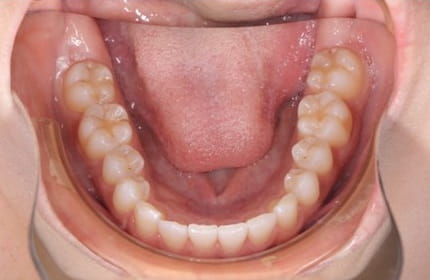

症例写真

Before

After